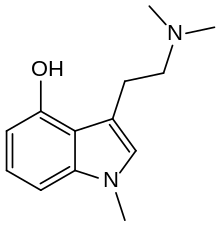

Substituted tryptamines, or serotonin analogues, are organic compounds which may be thought of as being derived from tryptamine itself. The molecular structures of all tryptamines contain an indole ring, joined to an amino (NH2) group via an ethyl (−CH2–CH2−) sidechain. In substituted tryptamines, the indole ring, sidechain, and/or amino group are modified by substituting another group for one of the hydrogen (H) atoms.

| Chemical structure | Short Name | Origin | Ring Substitution | RN1 | RN2 | Full Name | CAS Number |

|---|---|---|---|---|---|---|---|

| 1-Methylpsilocin | artificial | 1-CH3, 4-OH | CH3 | CH3 | 1-Methyl-3-[2-(N,N-dimethylamino)ethyl]-4-hydroxyindole | 1465-16-3 |